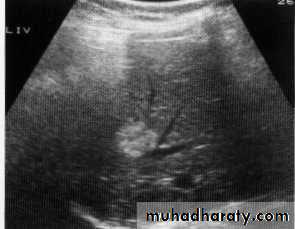

Hepatic mets.